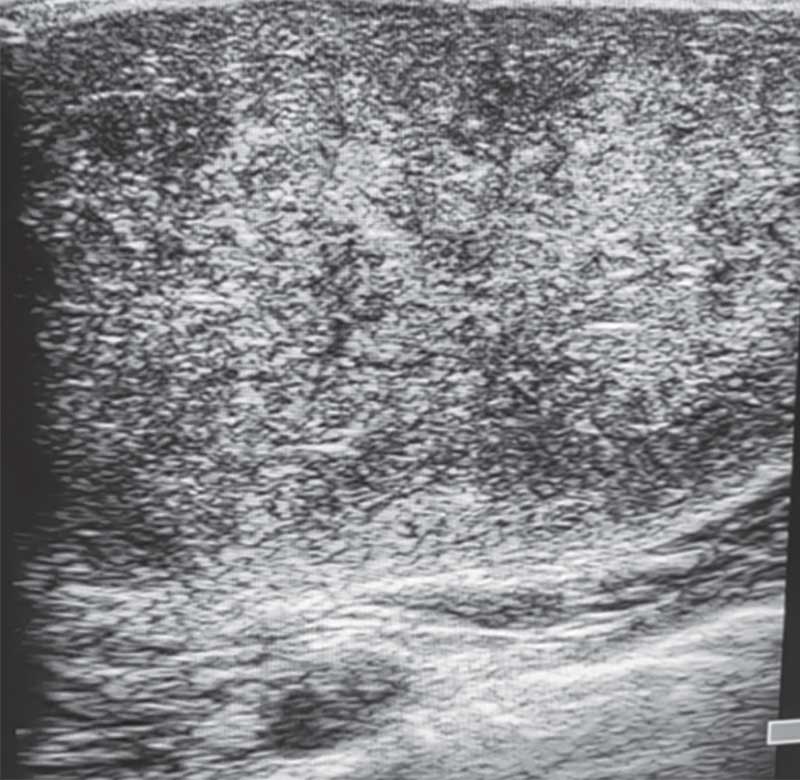

Рис. 3. Ювенильная фиброаденома правой молочной железы у 15-летней девочки

На УЗ-картине солидное, гипоэхогенное по сравнению с тканью МЖ образование однородной структуры, с четкими контурами. Нередко наблюдается дорсальное псевдоусиление без акустической тени (рис. 3–5) [5, 7, 10].